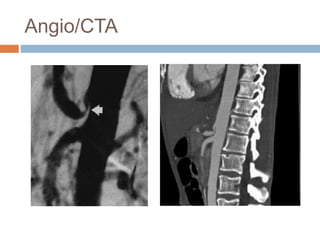

Angio/CTA

Angioplasty